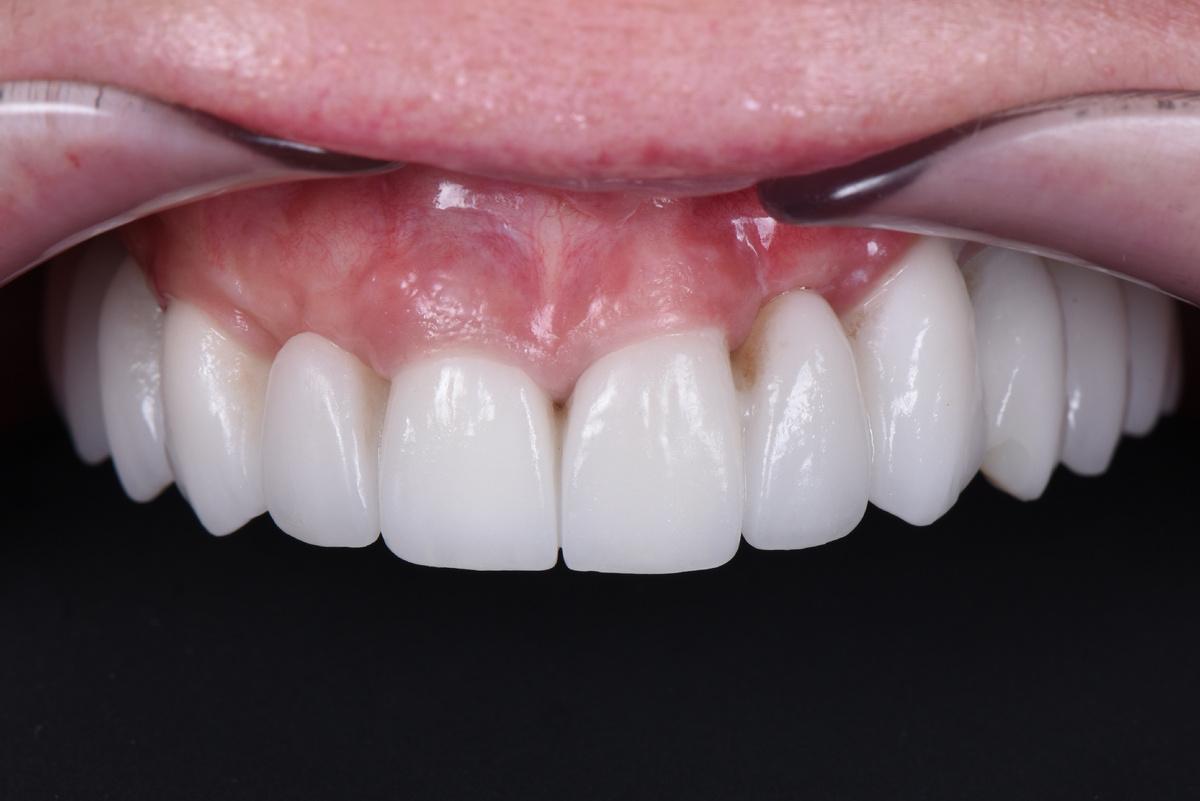

Ещё через 2 месяца — установка формирователей и мягкотканная пластика для формирования массива кератинизированной десны в области имплантации

И, наконец, последний хирургический этап — установка 2 имплантатов в 3-ем сегменте слева. В данной области, где дефицит кости был самым катастрофическим, остеоинтеграция заняла 12 месяцев ️ Результат через месяц после установки формирователей и процедуры обязательного восстановления мягких тканей:

Завершающий этап — после протезирования на имплантатах на нижней челюсти слева, в той области, где костная ткань восстанавливалась дольше всего